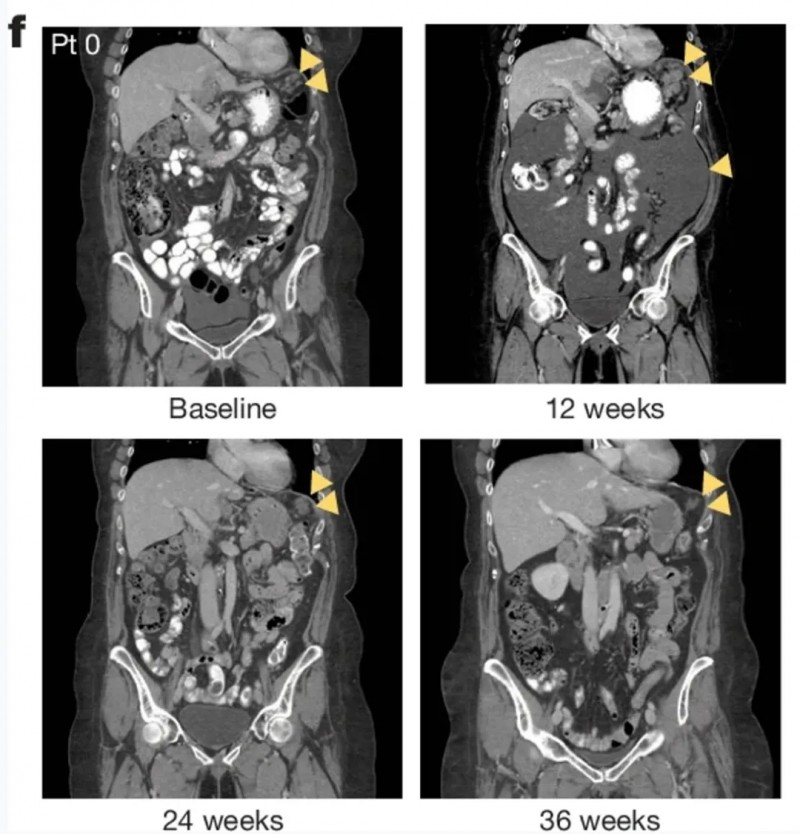

值得一提的是,其中一例代表性患者的计算机断层扫描(CT)图像显示,治疗后肿瘤病灶随时间呈现明显缓解趋势(详见下图),进一步验证了该突变对应的治疗获益。

▲图源“Nature”,版权归原作者所有,如无意中侵犯了知识产权,请联系我们删除